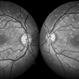

- Circinate Retinopathy

- Dr Vishal Gupta, INHS Asvini, Mumbai, INDIA

- Imaging device

- Fundus camera

- fundus image of 56-year-old male patient with circinate retinopathy.